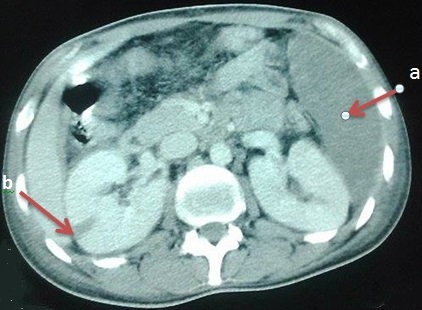

La granulomatose avec polyangéite (GPA) est une vascularite nécrosante systémique, caractérisée par une inflammation granulomateuse, une nécrose tissulaire et une vascularite touchant les vaisseaux de moyen et, surtout, de petit calibre. L'infarctus splénique est une complicationtrès rare de la GPA, sa survenue est grave en raison des potentielles complications hémorragiques pouvant engager le pronostic vital. Nous rapportons l'observation d'un jeune patient âgé de 26 ans, dont le diagnostic de GPA a été posé il y a une semaine, et retenu devant la présence de 3 critères de l'ACR: atteinte ORL, anomalies à la radiologie pulmonaire, et atteinte rénale. Il a présenté subitement des douleurs abdominales prédominant à gauche, l'examen physique a objectivé une sensibilité du flanc gauche. Devant l'aggravation de la symptomatologie digestive, un angioscanner abdominal a été pratiqué montrant un infarctus splénique et un défaut de rehaussement segmentaire du rein droit. Le patient était mis sous corticothérapie et cyclophosphamide. Deux mois plus tard, le patient était ré-hospitalisé pour apparition d'un purpura pétéchial rapidement extensif, une fièvre en rapport avec un sepsis, une aggravation rapide de l'atteinte pulmonaire et rénale à l'origine de son décès.